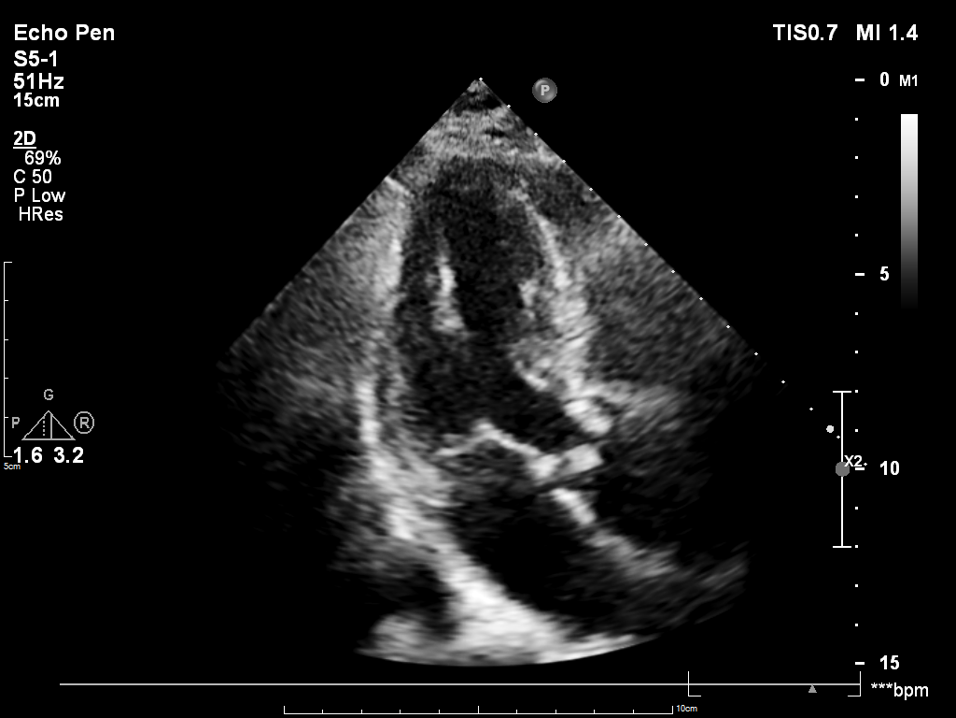

检查结果-术中超声

检查结果-即刻超声

动脉瓣瓣周轻度反流。

经主动脉口收缩期血流最大速度约1.5m/s,最大跨瓣压差约10mmHg。